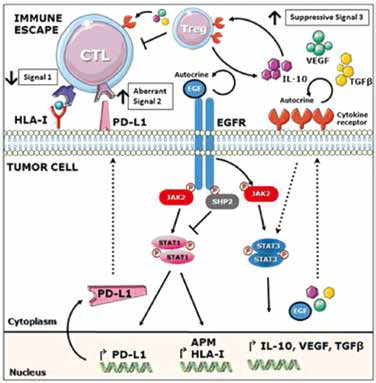

EGFR-TKI联合PD-L1抗体的顺序和时机对肺炎…

EGFR-TKI联合PD-L1抗体的顺序和时机对肺炎…

2019-10-15 08:38:53

上海市肺科医院周彩存教授等报告的临床前研究显示,EGFR-TKI联合PD-L1抗体的顺序和时机可能会影响肺炎的严重程度。(Lung Cancer. 2019年9月19日在线版 doi: 10.1016/j.lun…